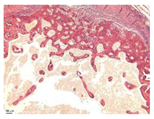

| Point | Type of Microscopy | ||||

|---|---|---|---|---|---|

| Standard Light | Standard Light | Polarization | Standard Light | Phase Contrast | |

| Staining with Hematoxylin–Eosin | Staining with Picrosirius Red | Staining with Picrosirius Red | Staining with Hematoxylin–Eosin | Staining with Hematoxylin–Eosin | |

| 3 | ![]() | ![]() | ![]() | ![]() | ![]() |

| 5 | ![]() | ![]() | ![]() | ![]() | ![]() |

| 8 | ![]() | ![]() | ![]() | ![]() | ![]() |